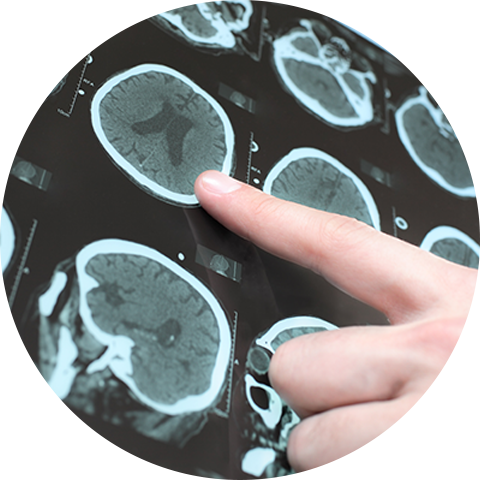

NEUROFIM es una clínica especializada en realizar estudios clínicos neurológicos y neurofisiológicos en Cuernavaca, Morelos. Contamos con más de 20 años de experiencia que nos respaldan y avalan como su mejor opción.

En NEUROFIM contamos con tecnología de primera generación para realizar estudios clínicos neurológicos, así como personal capacitado conformado por médicos especialistas en medicina familiar actualizados con cursos en neurología y neurofisiología. Nuestra prioridad es brindarle diagnósticos precisos y oportunos en cualquier momento.